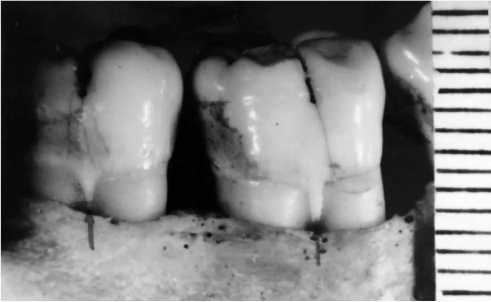

The study revealed the following: the skull was of medium size (Fig. 1) and brachycranial shape (cranial index 87.5%); morphological and metric parameters indicated the male sex; morphological features of the studied bones indicated the age of 30–39 years. The age was established using the methods of Zvyagin (1975) [4] and Acsady Nemeskeri in the edition of Sjøvol (1975) [5]; when determining the race of the skull, the method of Zvyagin (1981) was used [6]. The studied skull belonged to the mixed racial group (among the identifying features of the skull there were eight presumably Caucasian indicators, 12 presumably Asian indicators, the rest of the indicators are undetermined). Examination of the teeth revealed shovel-shaped incisors on the upper jaw, torsion and inward displacement of the second upper incisor (Fig. 2). In addition, enamel leaks were found on the first and second large molars of the lower jaw (Fig. 3).

Fig. 2. Spatulate shape of the upper incisors and inward twisting of the upper second incisor.